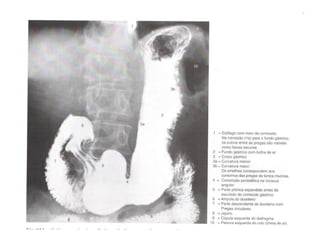

Estomago Características gerais P arte mais dilatada do trato gastrointestinal Possui formato em forma de “J” L ocalizado  Regiões epigástricas, umbelical e hipocôndrio esquerdo entre a parte abdominal do esofago e o intestino delgado

Localização do estomago entre o esofago e o intestino delgado

Divisão regional do estomago Cardia Localiza-se ao redor da abertura do esofago no estomago F undo gastrico A rea acima do ostio cardico; 5 º  EIE C orpo do estomago M aior regiao do estomago, intermediaria P arte pilorica P arte terminal do estomago, dividida em:  antro pilorico e canal pilorico

Fundo Corpo Antro pilórico Ampola duodenal

Relações anatômicas Fundo  – hemicúpula diafragmática  E. Face anterior  – diafragma na região fúndica. -  lobo E do fígado.  - parede abdominal anterior. Face posterior   –  superior  – parte do diafragma, baço, supra-renal E.  -  inferior  – corpo / cauda do pâncreas, mesocólon transverso.

Interior do estomago Mucosa acastanhada e rosea P regas gastricas (longitudinais) M ais acentuadas na curvatura maior e e parte pilorica

Piloro Incisura  angular A mpola duodenal Artérias e veias gastromentais D  Artérias e veias gástricas E  Artérias e veias gastromentais E Incisura  cárdica Lig. Hepato duodenal Artérias e veias gástricas D

Óstio pilórico Localizado a direita da linha mediana em um plano que passa atraves da margem inferior de L1 M arcada na superfície pela  constrição pilórica R odeado por um anel espesso de musculo gastrico circular, o  esfincter pilorico